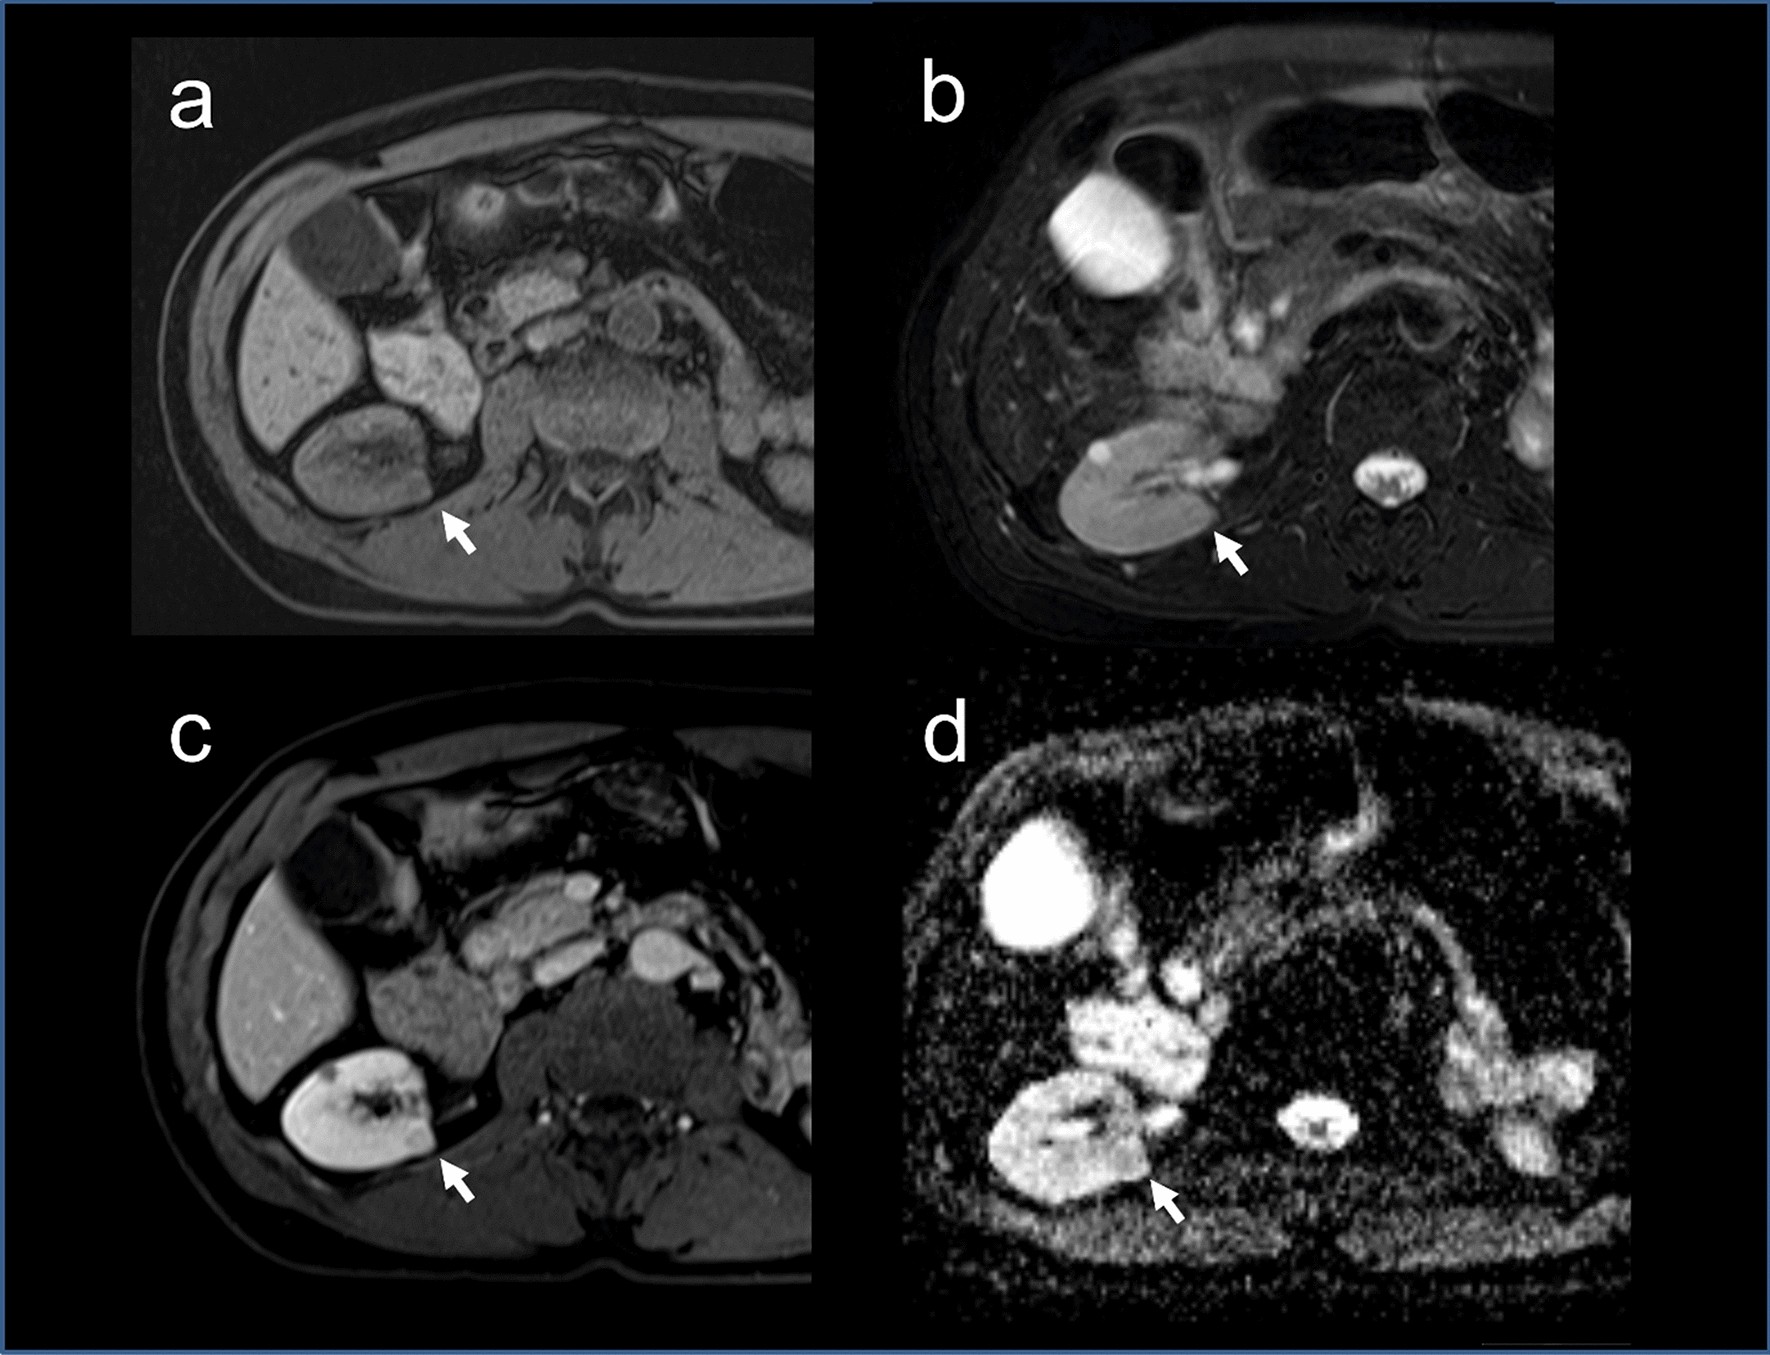

Figure 1

Radiological diagnosis of RCC in a GIST patient. MRI showing a coronal section of the abdomen with renal lesion (arrows). (a) T1 FS image showing a mild low signal intensity of a right posterior 8 mm renal mass. (b) T2 FS image showing increased intensity of the renal lesion. (c) T1 FS image showing hyperenhancement of the lesion after contrast injection. d. ADC MAP showing diffuse restriction of the lesion.